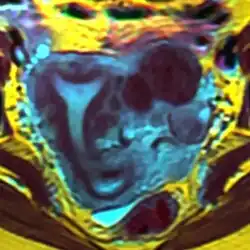

Arcuate uterus (marked in red) seen on MRI | |

The arcuate uterus is a form of a uterine anomaly or variation where the uterine cavity displays a concave contour towards the fundus. Normally the uterine cavity is straight or convex towards the fundus on anterior-posterior imaging, but in the arcuate uterus the myometrium of the fundus dips into the cavity and may form a small septation. The distinction between an arcuate uterus and a septate uterus is not standardized.